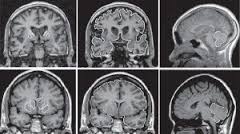

Ukoliko osoba oseti promene u pokretima, emocionalnom stanju ili mentalnoj sposobnosti, trebalo bi da konsultuje lekara. Iako porodični lekar može da dijagnostikuje Hantingtonovu bolest, većina ljudi će otići kod neurologa da potvrde dijagnozu i potraže pomoć u rešavanju različitih simptoma. Hantingtonova bolest se, po pravilu, dijagnostikuje neurološkim pregledom, uključujući imidžing tehnike mozga ili genetsko testiranje, kao i pregled porodične anamneze.